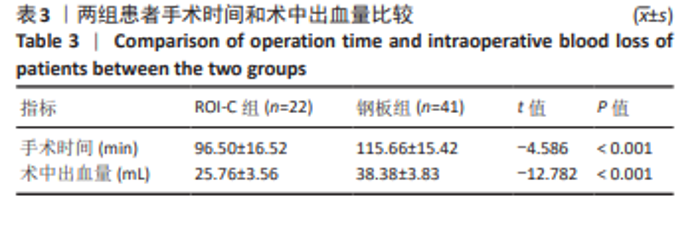

2.7 术后并发症评估 2.7.1 吞咽困难情况分析 在ROI-C组中,术后出现吞咽困难的病患数为4例,占该组总数的18%(4/22),此症状在术后3个月内自行缓解。相比之下,钢板组术后发生吞咽困难的患者较多,共计14例,发生率为34%(14/41);术后3个月时,钢板组内仍有7例(17%)患者持续存在吞咽困难;至术后6个月的随访时,这些患者的吞咽困难症状均得到显著改善或消失。统计结果显示,两组间在术后吞咽困难的发生率上未见显著性差异(χ2=1.788,P=0.181);ROI-C组术后3个月吞咽困难发生率显著低于钢板组(Fisher确切概率法P=0.041)。 2.7.2 邻近节段退变情况分析 ROI-C组与钢板组患者在术后3,6个月的时间点上,均未报告有邻近节段退变发生。术后12个月,ROI-C组中观察到邻近节段退变病例1例,占比5%(1/22);而钢板组内则出现3例邻近节段退变,占比7%(3/41),两组差异无显著性意义(χ2=0.029,P=0.866)。 两组术后12个月的上邻近节段和下邻近节段椎间隙高度均较术后即刻明显降低,但钢板组邻近椎间隙高度下降程度较ROI-C组明显增高,差异有显著性意义(P < 0.05)。两组间术前、术后即刻、术后3,6,12个月的C2-7 Cobb角、T1倾斜角、椎间隙高度相比差异均无显著性意义(P > 0.05)。 2.8 植入物与宿主的生物相容性 术后6个月时,ROI-C组出现1例未融合(5%),钢板组出现1例(2%);术后12个月时两组患者全部获得融合,两组间无明显差异(P < 0.05)。两组术后均未出现植入物周围感染、过敏反应、免疫反应及排斥反应。部分患者(ROI-C组3例、钢板组9例)术后出现体温轻度升高(小于38 ℃),在术后3 d内均得到恢复。术后各时间节点均未发现植入物破损、松动、脱落。 2.9 典型病例 影像学资料见图3,4。"